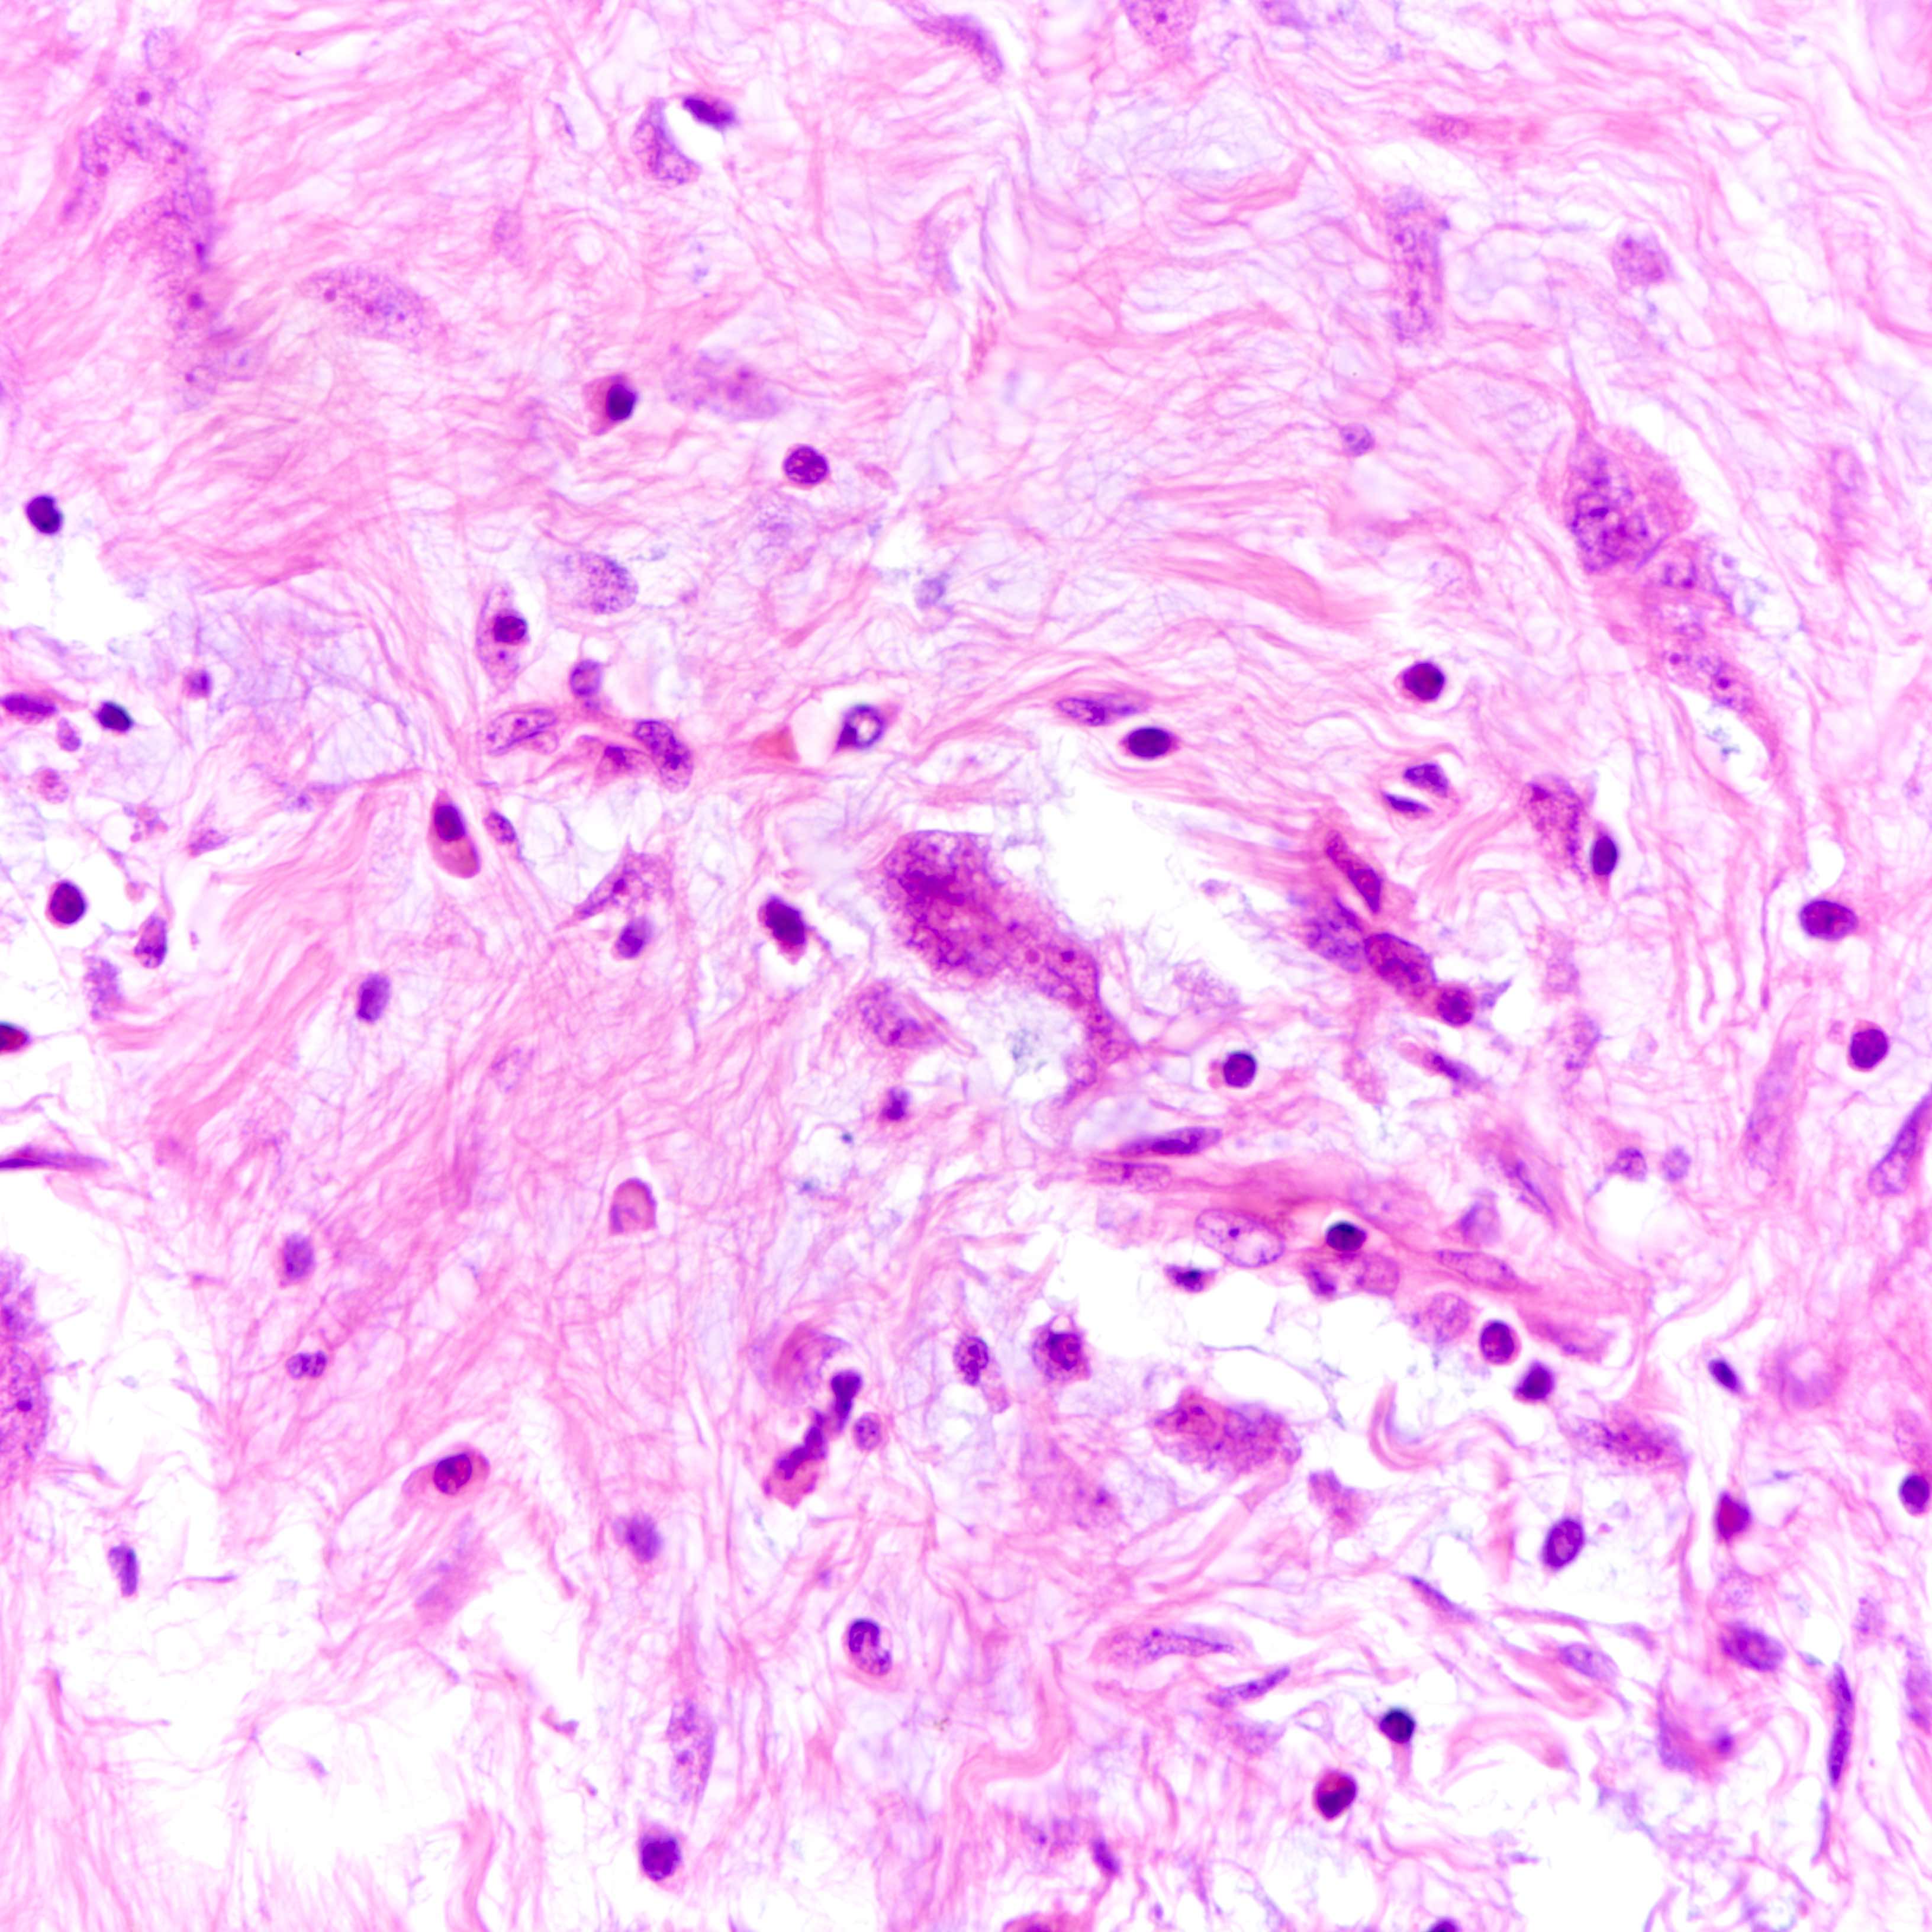

Microscopic (histologic) images

Contributed by Joshua J.X. Li, M.B.Ch.B. and Gary M. Tse, M.B.B.S.

Borderline phyllodes tumor